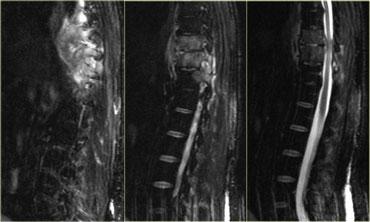

Bên trái là hình ảnh của một bệnh nhân mắc một bệnh lý thường bị bỏ sót nhất tại khoa cấp cứu, dẫn đến nguyên nhân hàng đầu gây ra các vụ kiện tụng y tế.

Hãy nghiên cứu các hình ảnh trước khi tiếp tục.

Lưu ý dấu hiệu giãn rộng dải cạnh sống ở cả bên trái và bên phải trên phim X-quang tư thế thẳng (PA).

Trên phim X-quang tư thế nghiêng, khoang đĩa đệm bị hẹp nặng.

Chẩn đoán là viêm đĩa đệm đốt sống (discitis).

Trên MRI, có thể nhận thấy phù nề của các mô mềm và tín hiệu cao của đĩa đệm.